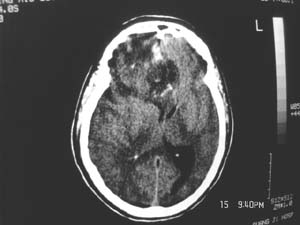

女,60岁,反复头痛3天,呕吐3小时伴昏迷10分钟入院检查。

右额叶占位,有占位效应,中线偏移,病灶位于镰旁,呈囊实性并有钙化,

考虑:1.脑膜瘤。2.胶质瘤。

理由:1.病灶位于前颅凹及镰旁,有明显占位效应---支持脑膜瘤。

2.病灶呈囊实质性并有条状钙化,符合胶质瘤改变;

另外也不排除包虫病的可能。

右额叶占位,有占位效应,中线偏移,病灶位于镰旁,呈囊实性并有钙化 kaolv  少枝胶质瘤。胶质瘤。

结合病史这么短,病情进展迅速,从常见病多发病方面考虑,比较符合脑血管病,故首先考虑出血性脑梗塞;

其次考虑脑肿瘤,是否并有瘤卒中,还是钙化我觉得ct值很重要;

病变范围较大,累及左额叶,内见钙化。及高密度灶。考虑;胶母伴卒中可能大。